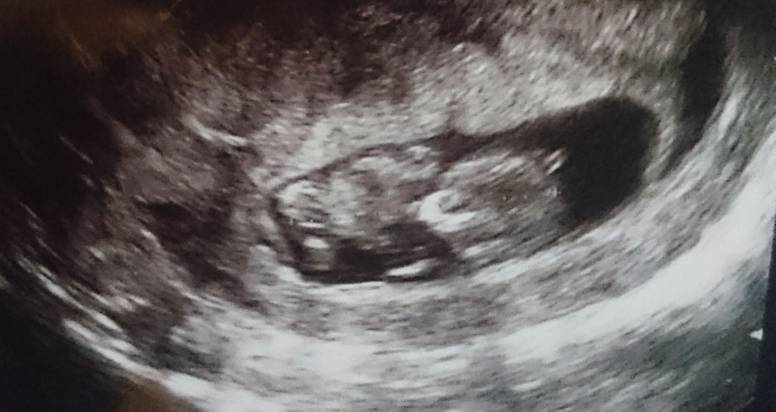

Ja już też po wizycie z której myślałam że wyjadę nie zadowolona bo bez USG ... Aleeeee widziałam, słyszałam, ruszał się, nie mógł dobrze zdjęcia zrobić (bo rozmazane wychodziło co zastopowal);))!! ma niecałe 4,5 cm. Mówił że to tylko tak na sprawdzenie co u niego słychać i by serduszka posłuchać. Policzyl mi jako bez wizyty USG. ;) trzy kg mniej wagi czyli teraz 60 kg. Kolejna wizyta 13.06 to badanie USG takie na sprawdzenie czy wszytko w porządku (genetyczne). Mówił nam o testach PEPPA itd. Ale raczej się nie zdecyduje. Mam koniecznie powtórzyć badania TSH bo poprzednio wyszło mi 3,10. No i chyba tyle. Aaaaaa no i ten nieszczęsny krwiak nadal jest...i leki w dalszym ciągu mam brać. Mąż na koniec powiedział czy zdjęcie wydrukuje i wydrukowal, a myślałam że tylko posłucham serca i wyłączy ekran, a tu zdziwienie! W ogóle gadał jak najety z lekarzem chyba więcej mówił niż ja i każdy poród opisał szczegółowo i chwalił się że był i że tym razem też nie odpuści. Hehe Pozdrawiamy. Jestem taka szczęśliwa [emoji4]

......:::::::::11tydz i 2dni::::::::.........